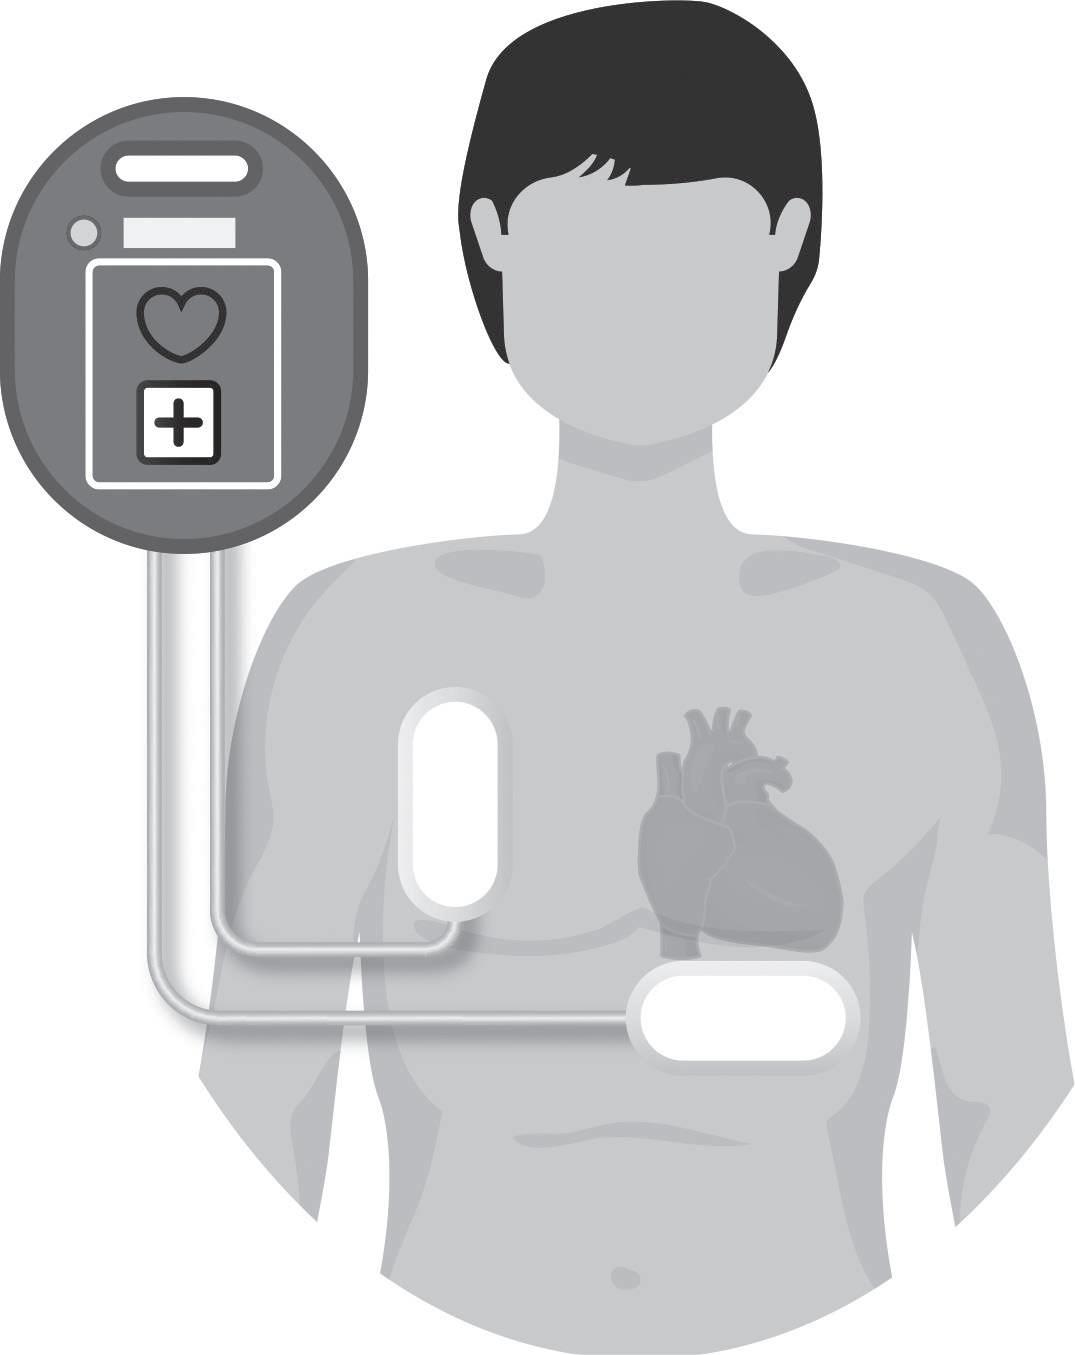

Vídeo 7.3.11

Este vídeo ilustra uma endocardite bacteriana aguda tricúspide associada com a presença de sondas de pacemaker e a implantação de uma prótese tricúspide para tratamento. Disponível em: https://www.youtube. com/watch?v=gpZae9B84tY. Consultado a 2 de agosto de 2023.